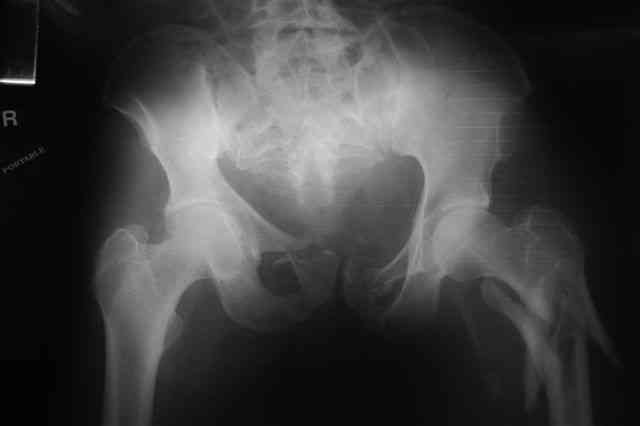

Я помню технику транссакральной фиксации тазового кольца длинными 5 мм Шанцами - повреждения типа В, в этом же случае задний отдел тоже вовлечен

т.е комбинированная нестабильность, поэтому вопрос - достаточно ли только двух Шанцев для стабилизации таза? Что вы думаете об anterior Right SI joint plating + tension band plating from the back.?

PS после фиксации бедра под Эопом посмотрел инлет и аутлет проекции, насколько репонируемо смещение правой половины таза *невооруженными*

руками - никаких шансов улучшить позицию иначе бы конечно воспользовался длинными Шанцами сразу после бедра.